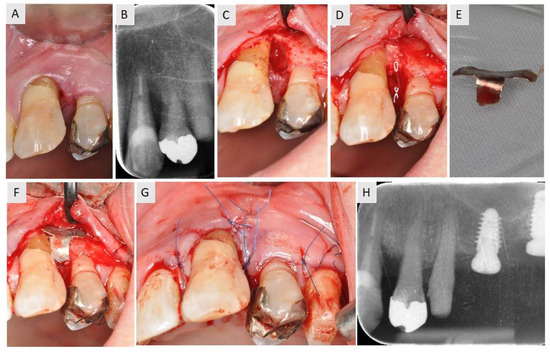

3.1. Case 1

3.2. Case 2